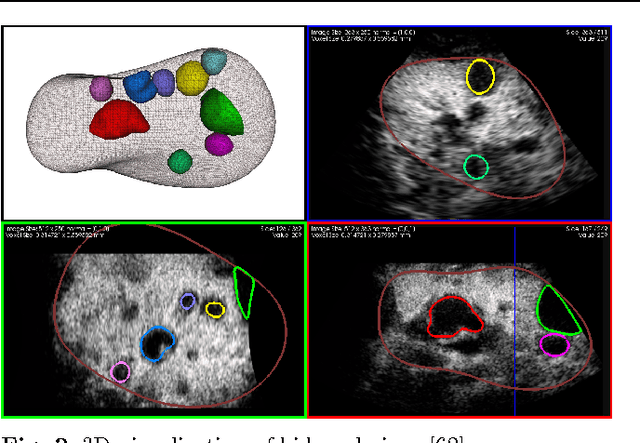

Abstract:Three-dimensional Ultrasound image segmentation methods are surveyed in this paper. The focus of this report is to investigate applications of these techniques and a review of the original ideas and concepts. Although many two-dimensional image segmentation in the literature have been considered as a three-dimensional approach by mistake but we review them as a three-dimensional technique. We select the studies that have addressed the problem of medical three-dimensional Ultrasound image segmentation utilizing their proposed techniques. The evaluation methods and comparison between them are presented and tabulated in terms of evaluation techniques, interactivity, and robustness.